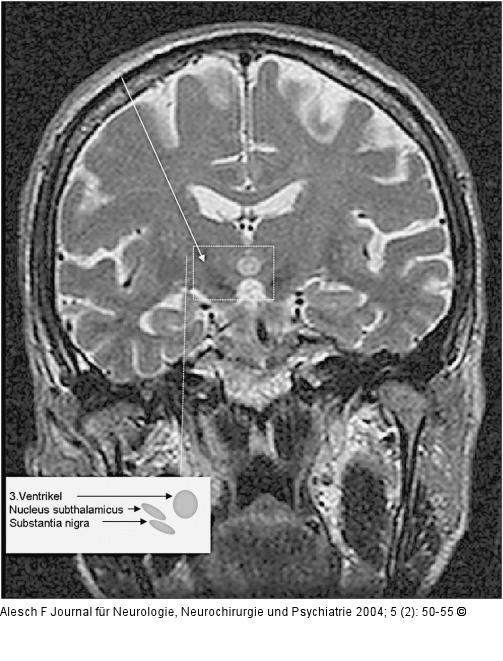

Abbildung 2: Morbus Parkinson - Nucleus subthalamicus Prächirurgische kernspintomographische Aufnahme des Nucleus subthalamicus. Die Kernspintomographie erlaubt eine sehr gute Visualisierung der Zielstruktur im subthalamischen und pallidalen Bereich. Die geometrische Genauigkeit dieser Untersuchung reicht aber nicht aus, um ausschließlich darauf die Zielpunktberechnung zu basieren. Hierzu werden weitere Untersuchungen, wie Computertomographie und stereotaktisches Röntgen, benötigt. |

Abbildung 2: Morbus Parkinson - Nucleus subthalamicus

Prächirurgische kernspintomographische Aufnahme des Nucleus subthalamicus. Die Kernspintomographie erlaubt eine sehr gute Visualisierung der Zielstruktur im subthalamischen und pallidalen Bereich. Die geometrische Genauigkeit dieser Untersuchung reicht aber nicht aus, um ausschließlich darauf die Zielpunktberechnung zu basieren. Hierzu werden weitere Untersuchungen, wie Computertomographie und stereotaktisches Röntgen, benötigt. |